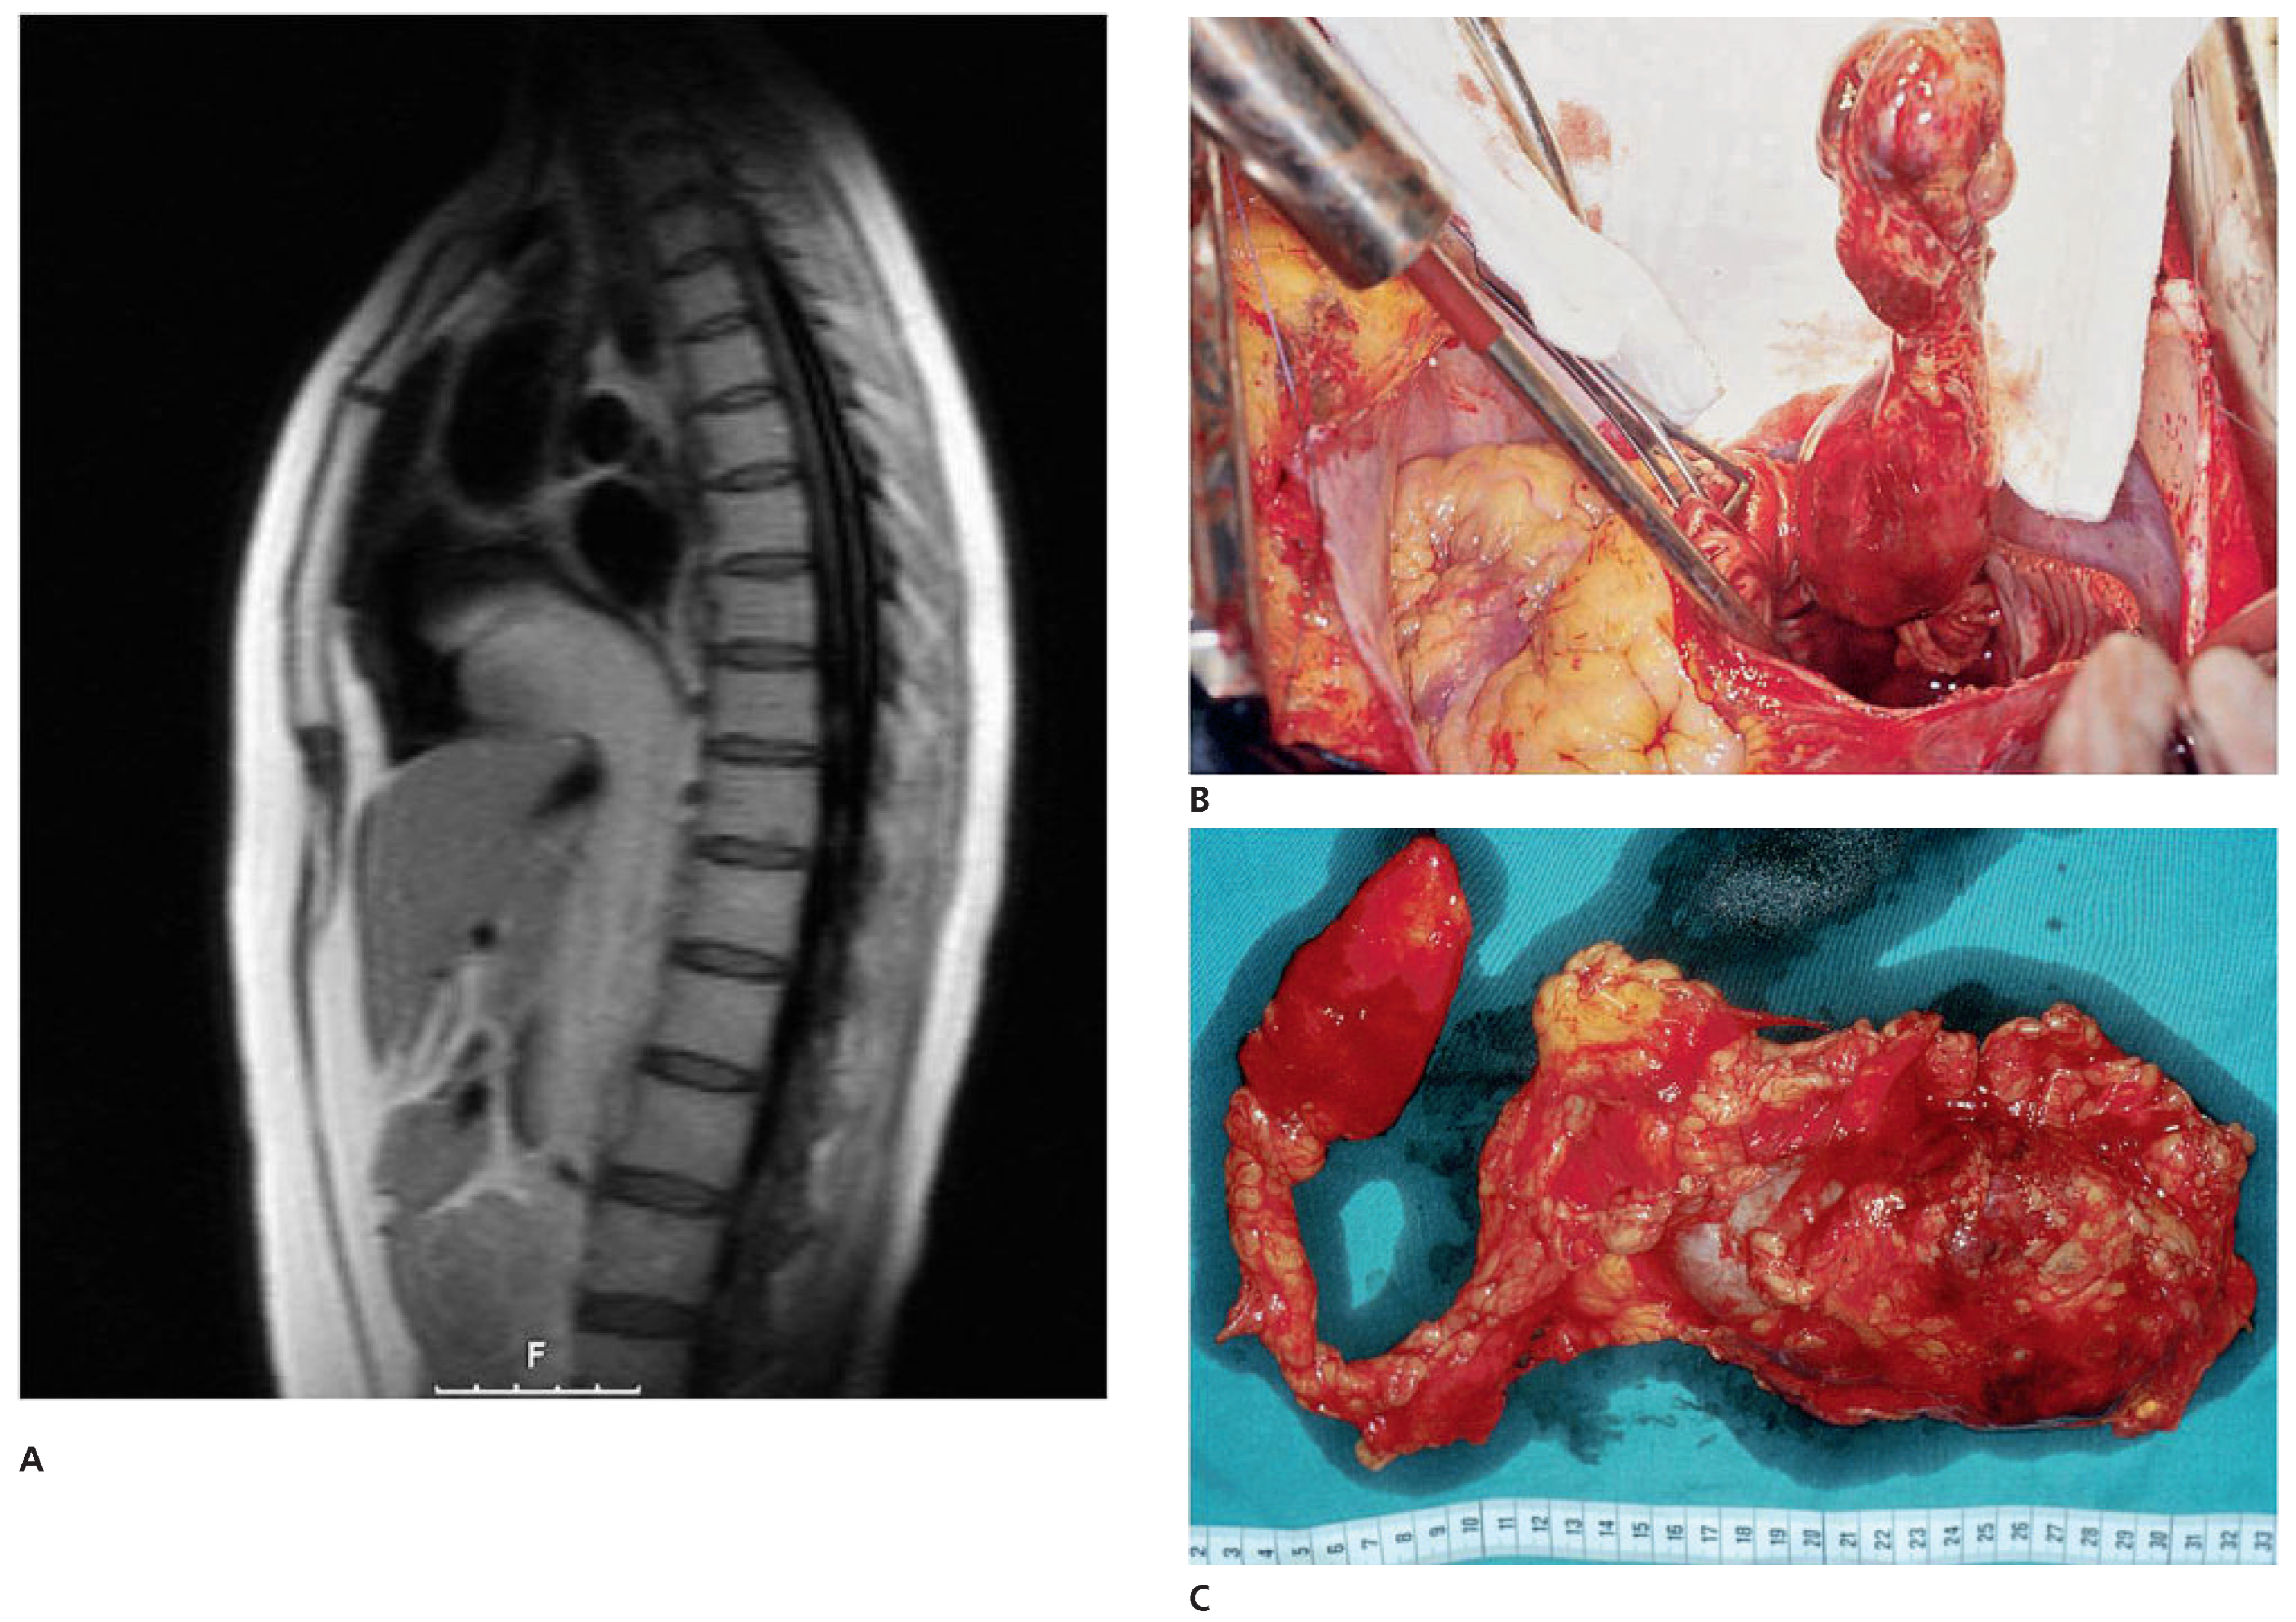

Case report 6: endometrial stromal sarcoma with extension into the right heart